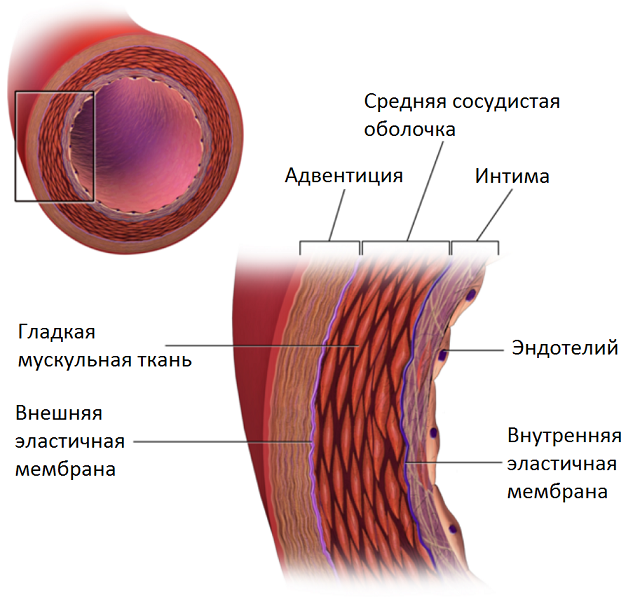

Как мы можем использовать эти знания по отношению к сосудам? Давайте взглянем на структуру одного из них:

На схемах этот момент обычно опускают, но в сосуде могут также присутствовать жир и образования кальция. Таким образом каждый воксель будет принадлежать к одной из тканей. После экспериментов оказалось что достаточно сделать следующие деления:

— жир

— стенка #1

— стенка #2

— контрастное вещество

— кальций

Распределение интенсивностей вокселей в каждом случае является нормальным. Т.е. у нас есть всё необходимое, чтобы, используя EM, найти параметры каждого источника.